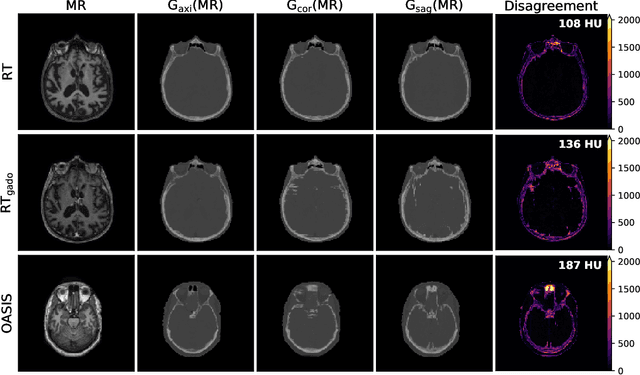

Abstract:Accurate MR-to-CT synthesis is a requirement for MR-only workflows in radiotherapy (RT) treatment planning. In recent years, deep learning-based approaches have shown impressive results in this field. However, to prevent downstream errors in RT treatment planning, it is important that deep learning models are only applied to data for which they are trained and that generated synthetic CT (sCT) images do not contain severe errors. For this, a mechanism for online quality control should be in place. In this work, we use an ensemble of sCT generators and assess their disagreement as a measure of uncertainty of the results. We show that this uncertainty measure can be used for two kinds of online quality control. First, to detect input images that are outside the expected distribution of MR images. Second, to identify sCT images that were generated from suitable MR images but potentially contain errors. Such automatic online quality control for sCT generation is likely to become an integral part of MR-only RT workflows.